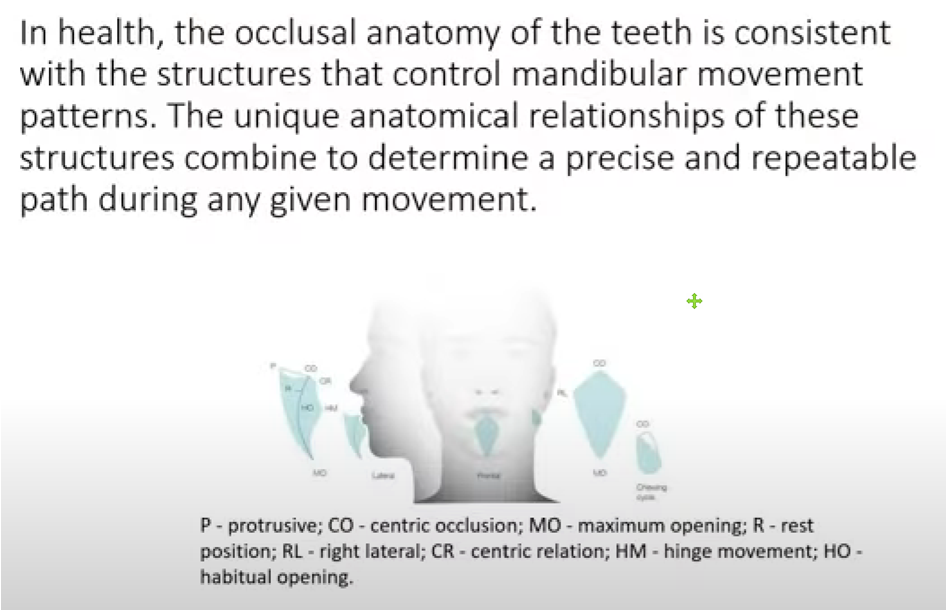

Occlusal line angle and maximum cusp position of upper and lower teeth

- Patent notice for tooth arrangement and production method of Maximal Intercuspation Position (MIP) occlusal line angle and maximum cusp position of upper and lower teeth

- The concept of Maximal Intercuspation Position (MIP) is the basis of the field of dentistry and orthodontics. However, it is challenging to pinpoint exactly when these ideas were first proposed because they have been developed and refined over a long period of time.

- occlusal line angle

- The occlusal angle line refers to the angle formed by the occlusal plane, which is essentially the imaginary surface where the upper and lower teeth come into contact during biting and chewing. This concept has been around for a long time and is critical to understanding bite mechanics, jaw alignment, and orthodontic treatment planning.

- Maximal Intercuspation Position (MIP) of the upper and lower teeth

MIP, also commonly referred to as "center bite," is the position where the upper and lower teeth come together in an optimal or "maximum" bite. This is an important concept in diagnosing and treating malocclusion as well as restorative dentistry.

- MIP, also commonly referred to as "center bite," is the position where the upper and lower teeth come together in an optimal or "maximum" bite. This is an important concept in diagnosing and treating malocclusion as well as restorative dentistry.

- History background

- Both concepts date back to early dental literature but have been refined extensively with the advent of modern dentistry in the 20th century.

- Although it is difficult to attribute the origin of these ideas to a specific date or individual, they have been an integral part of dental science for a considerable period of time and continue to evolve with ongoing research and clinical experience. The use of X-rays, 3D imaging, oral scans and computer modeling can also help to understand these concepts in more detail.

- According to the development of this concept, the use of digitally built occlusal retainers (positioners) on the articulator to control the growth and occlusal alignment of teeth can be accomplished based on the occlusal angle line.

- The concepts of the occlusal line angle and maximal intercuspation position (MIP) are fundamental in the field of dentistry and orthodontics. However, it's challenging to pinpoint exactly when these ideas were first proposed, as they have been developed and refined over a long period of time.

- Occlusal Line Angle

- The occlusal line angle refers to the angle formed by the occlusal plane, which is essentially the imaginary surface along which the upper and lower teeth make contact during biting and chewing. This concept has been around for a long time and is essential for understanding bite mechanics, jaw alignment, and orthodontic treatment planning.

- Maximal Intercuspation Position (MIP)

- MIP, also commonly referred to as "centric occlusion," is the position where the upper and lower teeth fit together in the most ideal or "maximum" interlocking way. It's a crucial concept for diagnosing and treating malocclusions, as well as for prosthetic dentistry.

- Historical Context

- Both concepts have roots going back to early dental literature but have been extensively refined with the advent of modern dentistry in the 20th century. The use of X-rays, 3D imaging, oral scan,and computer modeling has also helped in understanding these concepts in greater detail.

- While it's difficult to attribute the origination of these ideas to a specific date or individual, they have been integral parts of dental science for quite some time and continue to evolve with ongoing research and clinical experience.